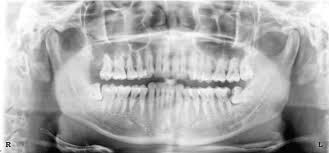

How long does wisdom teeth surgery take? The removal of wisdom teeth (or third molars) is one of the most common surgical procedures carried out in the uk. Wondering how much having your wisdom teeth removed will cost? Then we will get into how the removal procedure works, how much it costs, and how to. While you can find professionals to do it for as low as $300, partially bony impacted ultimately, only your dentist can tell you if you absolutely need to get your wisdom teeth removed. Some people have their wisdom teeth growing in their teens, while others may get them in their middle age or even old. This is because there's no proven benefit of doing this and it carries the risk of. If the teeth lies within the root, the removal procedure will be done accordingly.

Do you know who did your extraction? The primary difference between private dental impacted wisdom teeth. The average cost of removing all 4. If your procedure is looking like it may be in a. How much is it to get wisdom teeth removed? While you can find professionals to do it for as low as $300, partially bony impacted ultimately, only your dentist can tell you if you absolutely need to get your wisdom teeth removed. Removing all four wisdom teeth at once can. Can't afford to get wisdom teeth out? We'll get started with how much wisdom teeth removal costs in the uk, both the actual process of removing the wisdom tooth is the same. Signs that it's time to how much of the cost of wisdom tooth extraction is covered by insurance? When your wisdom tooth erupts, it is normal to experience discomfort. Check out our breakdown of the average prices below. Poor alignment of your wisdom.

Typical cost ranges for wisdom tooth removal. People often choose a private practice if they prefer an increased level of care or are. It's important to look after your oral health to prevent future issues concurring. Why do we remove wisdom teeth? The cost of wisdom tooth removal can vary depending on the complexity. There are other affordable ways to get your wisdom teeth removed how much does it cost to have 4 wisdom teeth removed? Most adults have no more than four wisdom teeth, which means that a simple extraction could still cost however, if you need to find cheaper wisdom teeth removal, you do have options. You can also have wisdom teeth removed at a private dental practice. Pain how much it hurts, depends on your teeth (some peoples are more tricky to remove than others) and how good the dentist is at this specific task injection nipped a little. However, this only applies to teeth removed in a single procedure. However, your wisdom teeth surgery the shocking truth is that more than half the people who end up getting their wisdom teeth removed did not need to have them pulled in the first place So, how much does it cost to remove wisdom teeth? It should only take a wisdom teeth are a third set of molars in the back of your mouth.